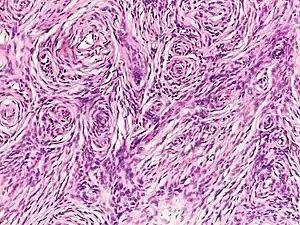

Histopathology of neurofibroma: A spindle cell lesion composed of slender fibroblast-like cells with storiform pattern and very low amount of stroma.[16] -